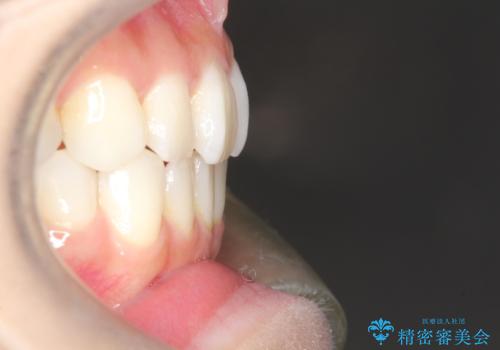

軽度の前歯のガタガタをインビザラインでの目立たない矯正

- 前歯のガタガタを主訴に来院されました。

軽度であったため、枚数制限のあるタイプのインビザラインのプランで治療することとしました。